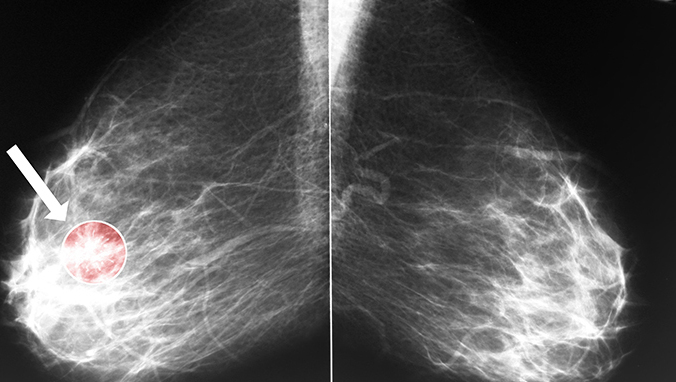

浸润性腺癌又叫做肺腺癌,它是属于肺癌的一种,跟小细胞肺癌相比,它的发病率相对而言比较低,所以在日常的生活中比较少见,大家对于这种疾病都不太熟悉。浸润性腺癌这种疾病主要是由于支气管黏膜上皮恶性增殖而造成的,很容易导致肺气肿的发生,从而造成支气管栓塞,这会严重的危害患者的生命安全,所以我们一定要引起足够的重视。在得了这种疾病之后,我们应该积极的采取措施进行治疗,以尽量减轻病情对身体的影响。